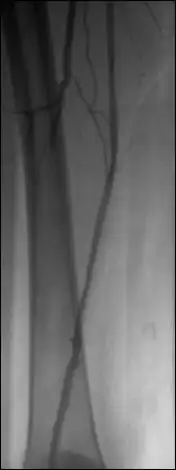

The image number used for the mask image is displayed – the first image of the sequence is the default mask. Browse through the sequence and adjust the WL/WW as needed. Click on the ‘current’ button to select another mask image.

Use the up/down arrows to shift the relative position of the mask and live images in single pixel increments in both horizontal (X) and vertical (Y) dimensions, if needed.